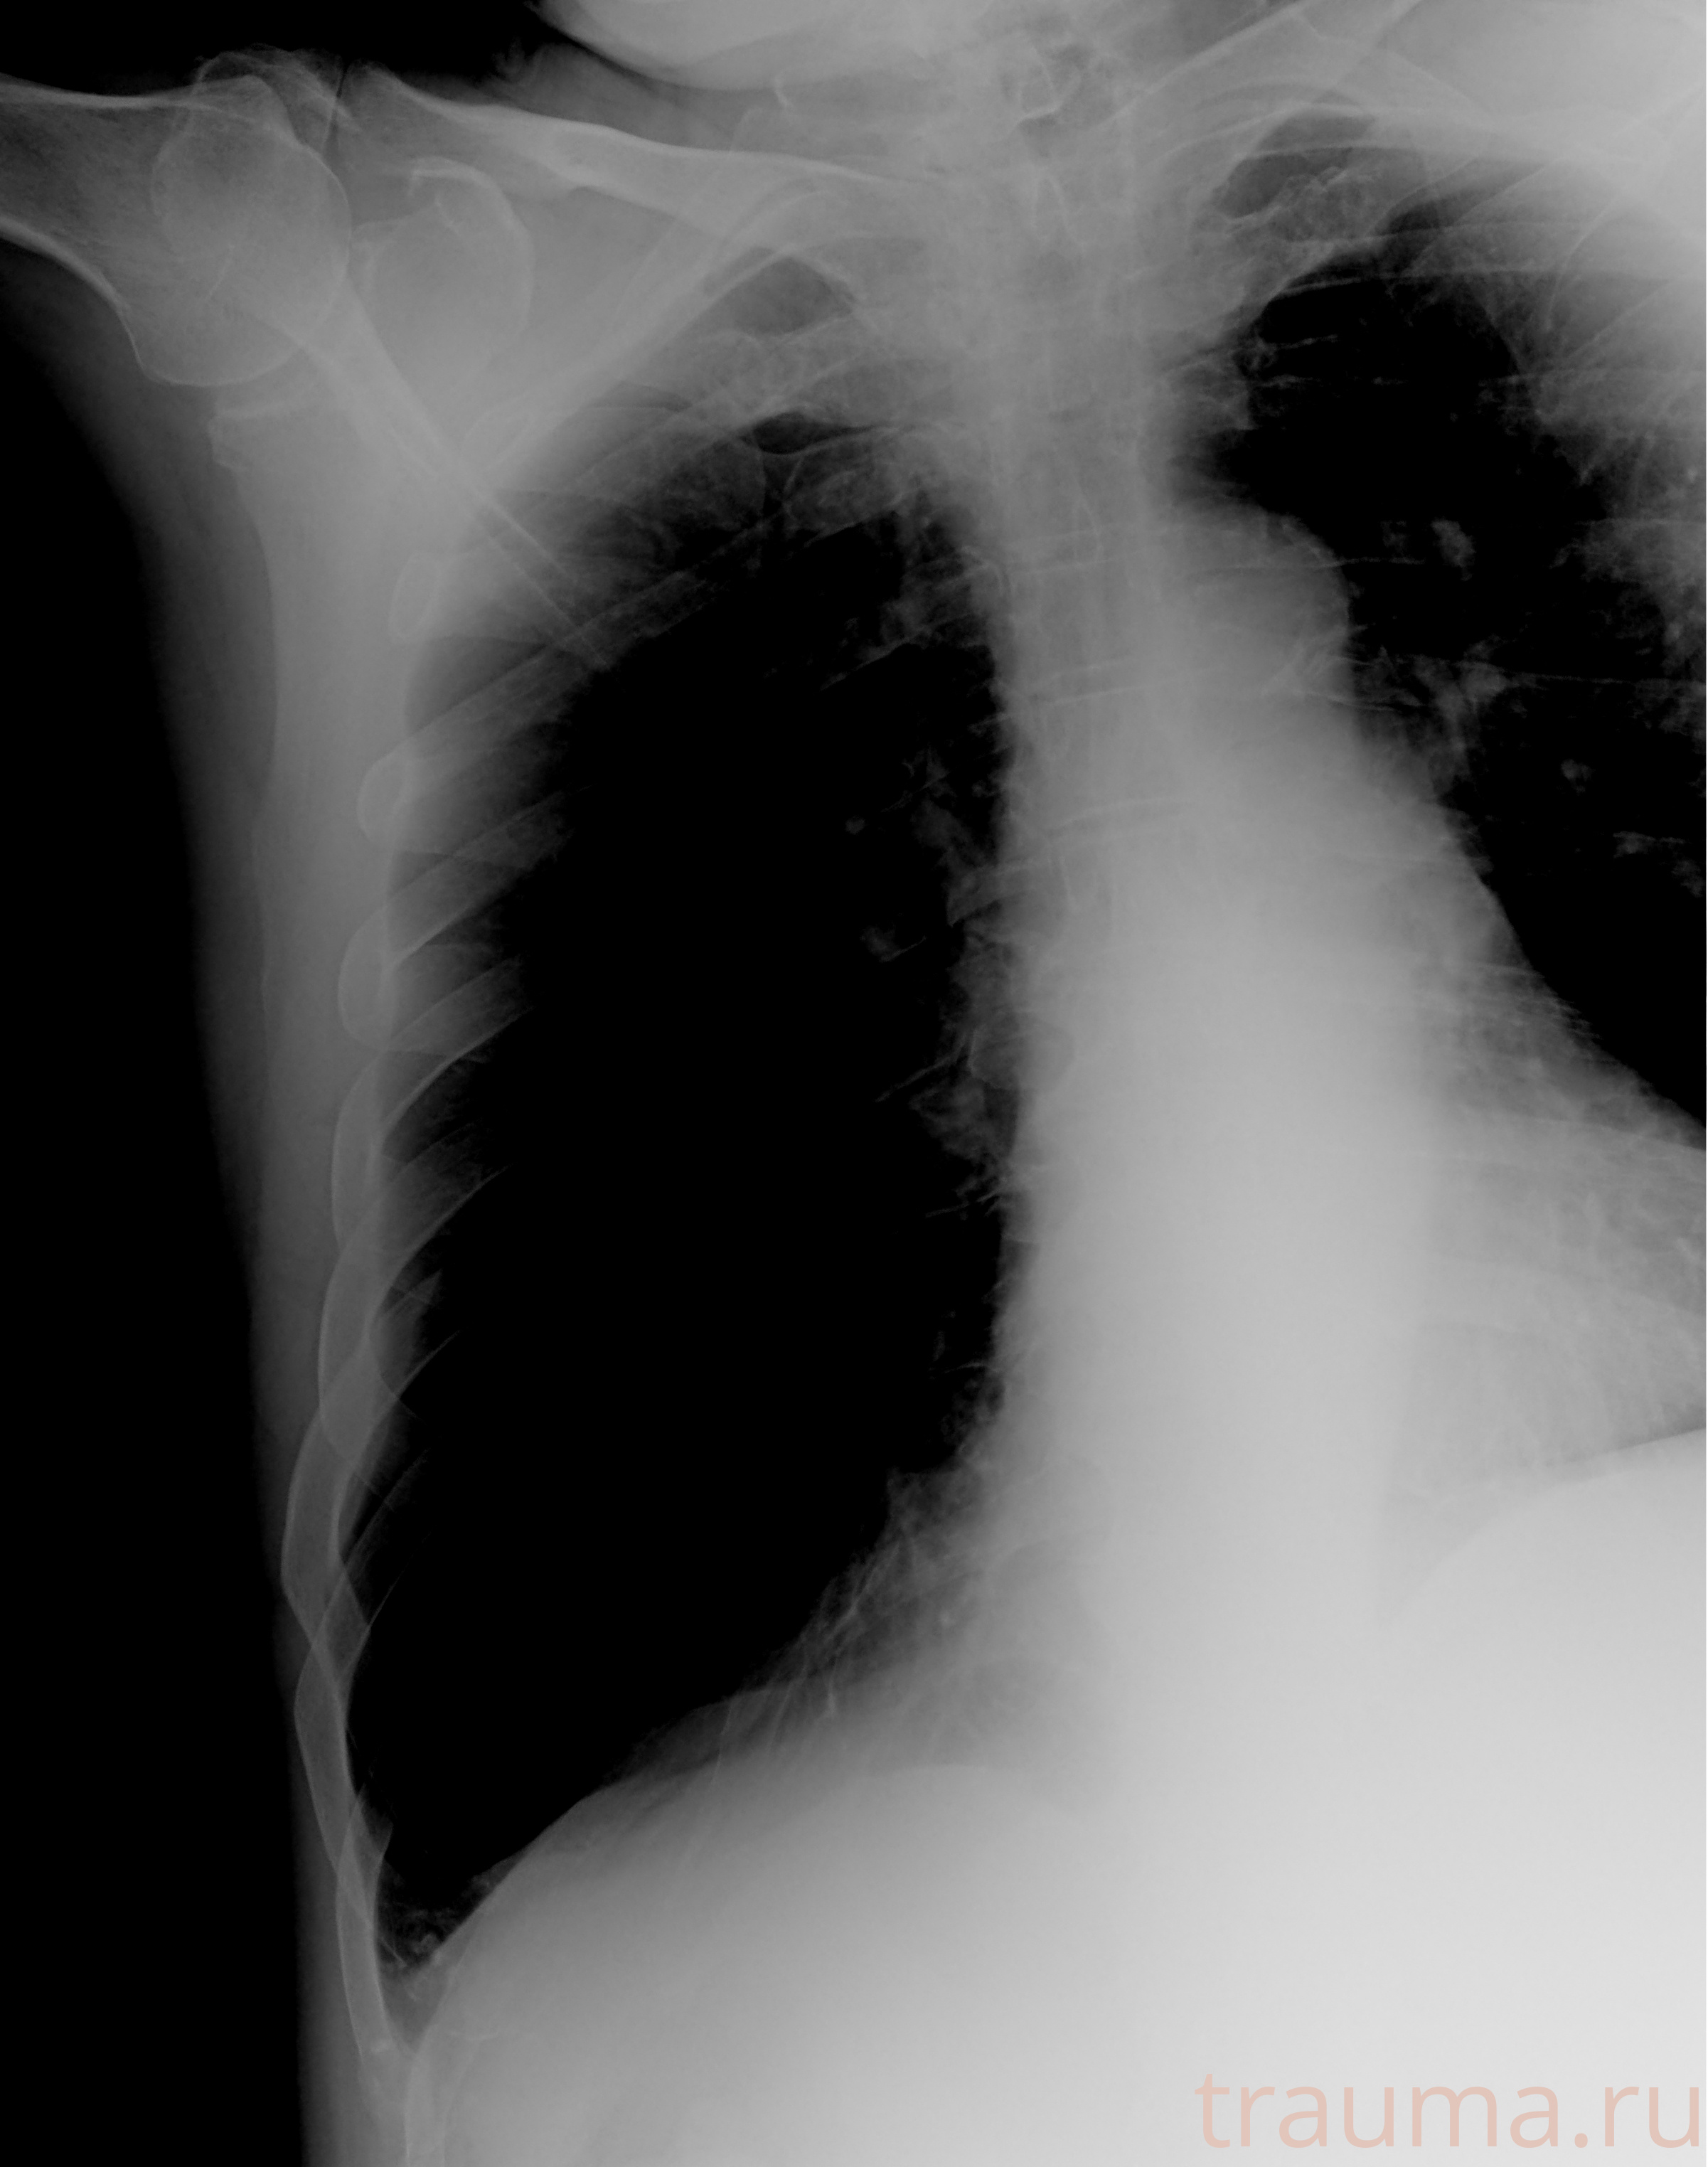

Рентгенограммы

Рентген на дому: по вашему адресу приезжает врач-рентгенолог, травматолог-ортопед с мобильным рентгеновским аппаратом, проводит диагностику травмы или заболевания, делает необходимые рентгенограммы, дает рекомендации по дальнейшему лечению. Получить качественные снимки в домашних условиях возможно благодаря уникальной методике, разработанной МосРентген Центром для института  Склифосовского

Яркость: 1   Контраст: 1   Инвертировать: 0 Увеличение: 1

Перетаскивайте мышь вверх/вниз для контраста, влево/право для яркости. Прокрутка колесом изменяет масштаб. Нажмите Сбросить для возврата к исходному изображению. При увеличении держите мышь в той области, которую хотите рассмотреть.